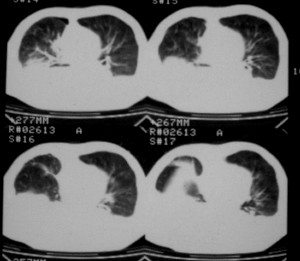

m ,60岁,右上肺ca术后一月。

右侧肺癌术后:肝内可见多个大小不等的低密度结节影。腹腔及双侧胸腔大量积液。考虑:肺癌并胸膜及肝脏转移。

纵隔淋巴结增大,双侧胸水。考虑术后残留,而非复发。

腹水,肝及右肾多发低密度影。考虑转移。

肝及右肾转移瘤,双侧胸水